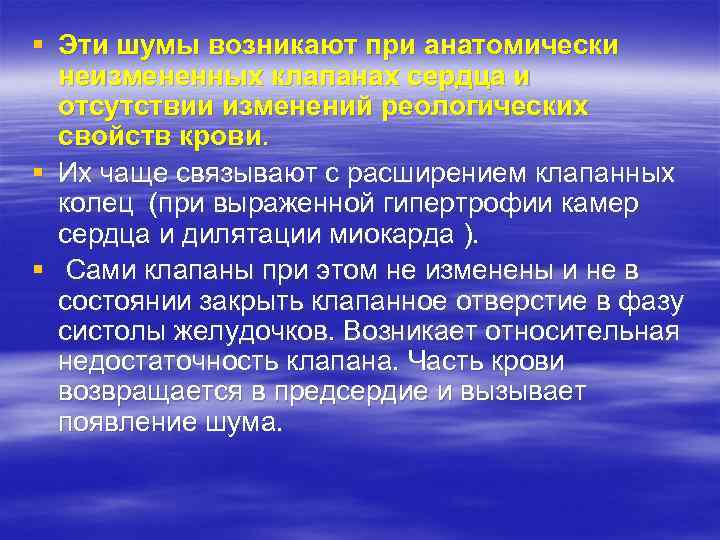

Шумы относительной недостаточности клапанов или относительного сужения клапанных отверстий связаны с нарушениями функции клапанного аппарата, в том числе при органических заболеваниях сердца

Шумы относительной недостаточности клапанов или относительного сужения клапанных отверстий связаны с нарушениями функции клапанного аппарата, в том числе при органических заболеваниях сердца

§ Эти шумы возникают при анатомически неизмененных клапанах сердца и отсутствии изменений реологических свойств крови. § Их чаще связывают с расширением клапанных колец (при выраженной гипертрофии камер сердца и дилятации миокарда ). § Сами клапаны при этом не изменены и не в состоянии закрыть клапанное отверстие в фазу систолы желудочков. Возникает относительная недостаточность клапана. Часть крови возвращается в предсердие и вызывает появление шума.

§ Эти шумы возникают при анатомически неизмененных клапанах сердца и отсутствии изменений реологических свойств крови. § Их чаще связывают с расширением клапанных колец (при выраженной гипертрофии камер сердца и дилятации миокарда ). § Сами клапаны при этом не изменены и не в состоянии закрыть клапанное отверстие в фазу систолы желудочков. Возникает относительная недостаточность клапана. Часть крови возвращается в предсердие и вызывает появление шума.